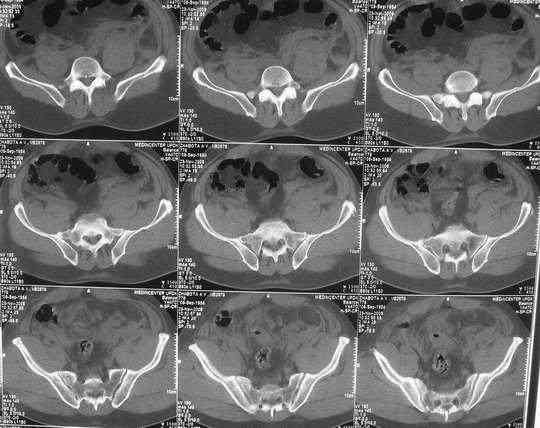

Уважаемые коллеги.У больного оскольчатые переломы левых лонной и седалищной костей со смещением, разрывом симфиза и распространением линии перелома на вертлужную впадину; переломы крыла левой подвздошной кости и правой боковой массы крестца без смещения; разрыв уретры.За последние годы пациент 6 раз оперирован на передней брюшной стенке (гнойный аппендицит срединным доступом, вентральная послеоперационная грыжа и паховые грыжи с обеих сторон, оперированные по 2 раза каждая). Остались 3 грубых втянутых рубца после этих операций. В настоящее время имеются 2-сторонние паховомошоночные грыжи (на одной из КТ-грамм указаны стрелками), из которых левая - значительных размеров. Мошонка огромная, однако, не напряженная. Состояние больного на сегодняшний день относительно удовлетворительное, кровопотеря компенсирована, мочевой пузырь катетеризирован.Прошу мнения сообщества по следующим вопросам: выполнять ли в таких условиях остеосинтез? Если да, то в какой последовательности (отдельно или одним этапом с герниотомией)? Объем остеосинтеза? Доступ?